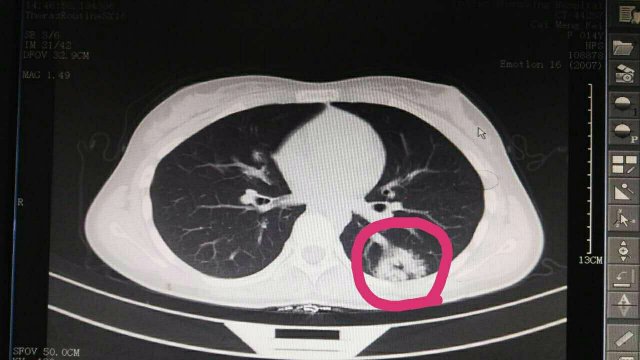

蔡**,女,14歲因“反覆頭暈3年余”,求診莆田及莆田各三級醫(yī)院,做過很多輔助檢查,均未確診,于2017-2-26日就診我院門診,接診是我院兒科林富醫(yī)師,經(jīng)過認(rèn)真仔細(xì)查體,發(fā)現(xiàn)患兒左側(cè)肩胛骨可聞及Ⅱ-Ⅲ/Ⅵ級收縮期雜音,為明確診斷,即刻請我院莊姞副主任醫(yī)師(原莆田市Di一醫(yī)院NICU主任)會診,查胸部CT發(fā)現(xiàn)左肺下葉背段血管畸形。莊姞副主任醫(yī)師告訴我們,部分型肺血管畸形如果不認(rèn)真查體是很難查體的到,年輕醫(yī)師能如此仔細(xì)查體,確診多家醫(yī)院未確診的疾病,不得不對林醫(yī)生豎起大拇指,通過此次經(jīng)歷,可見臨床醫(yī)生必須熟練掌握臨床三基的重要性。